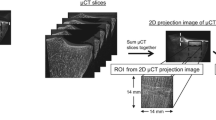

Bone texture analysis

The BMA device, equipped with a 12 × 12-cm detector (50 μ pixel size), was used to get the digitized anterior–posterior X-rays of these femurs. In order to standardize the acquisition technique, a ROI of 128 × 128 pixels was chosen in the femoral neck. The position of this ROI depends on that of two points selected by the operator. The device calculates the gray level average. If this lies within a certain range, further steps are allowed. If not, the software adapts the parameters of X-ray acquisition (kilovolt, milliampere second) and invites the operator to take another X-ray. This procedure aims at the homogenisation of the gray level average of the X-ray and therefore allows the comparison between different X-rays. This procedure was repeated with a ROI of the same size chosen in the greater trochanter and then in the intertrochanteric region. The precision of the technique was calculated by repeating X-ray acquisition and analysis three times for ten femurs without repositioning.

The selection of the ROIs was done according to anatomical landmarks in order to be reproducible. The femoral neck ROI was chosen by positioning the two points in the middle of the upper and the lower borders of the femoral neck so that the ROI lies in the middle of the femoral neck approximately at the anatomical Ward’s triangle (Fig. 1a). For the greater trochanter ROI, one point was positioned at the junction of the greater trochanter and the femoral neck, and the other, at the edge of the greater trochanter on a line perpendicular to the axis of the femur (Fig. 1b). For the intertrochanteric ROI, one point was positioned at the junction of the greater trochanter and the femoral neck, and the other, at the upper edge of the lesser trochanter (Fig. 1c). The texture parameters given by the device for each ROI are the fractal dimension (Hmean), the co-occurrence matrix, and the run length matrix.